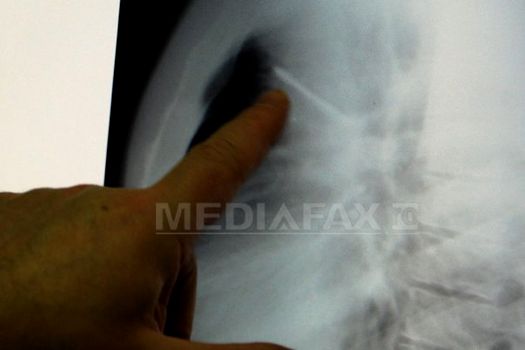

„Am operat un rănit căruia i-a intrat în plămân una dintre schije. A supravieţuit. Era un luptător rănit la începutul ostilităţilor, venea din Slaviansk”, la 200 de kilometri nord-est de Doneţk, a explicat Oleksandr Kuzneţov, şeful secţiei de chirurgie cardiacă de la spitalul Kalinin, arătând fotografii realizate în timpul operaţiei şi radiografiile făcute înaintea operaţiei, care arată clar o schijă.